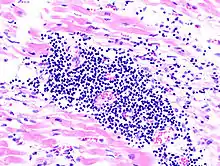

| thumb|Subakute Endokarditis durch Haemophilus parainfluenzae. |

Mikro: Zentral Bakterienkolonien in der Kapillare umsäumt von Immunozyten.

Mikro: Interstitielles lymphozytäres Infiltrat (kleine blaue Zellen), kaum Nekrosen.

| .JPG.webp) Virale Myokarditis bei Patient mit plötzlichem kongestiven Herzversagen, Autopsiepräparat, H&E. | .JPG.webp) idem. |